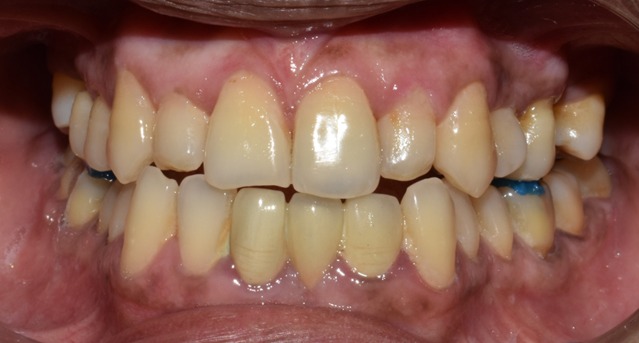

Before & After Results

At Aline Dent, we take pride in delivering visible and lasting improvements in our patients’ smiles. Our before-and-after results highlight the effectiveness of modern dental treatments combined with personalized care. This gallery showcases real dental cases treated at our clinic, giving you a clear idea of how different dental concerns can be corrected with the right treatment approach.

From minor corrections to complete smile enhancements, these teeth transformation results demonstrate how professional dental care can improve both oral health and appearance. Our experienced dental team carefully evaluates each patient’s needs and creates customized treatment plans to achieve natural, healthy, and confident smiles.

In this gallery, you will find a variety of smile makeover cases, including treatments for crooked teeth, gaps, discoloration, damaged teeth, and other common dental concerns.